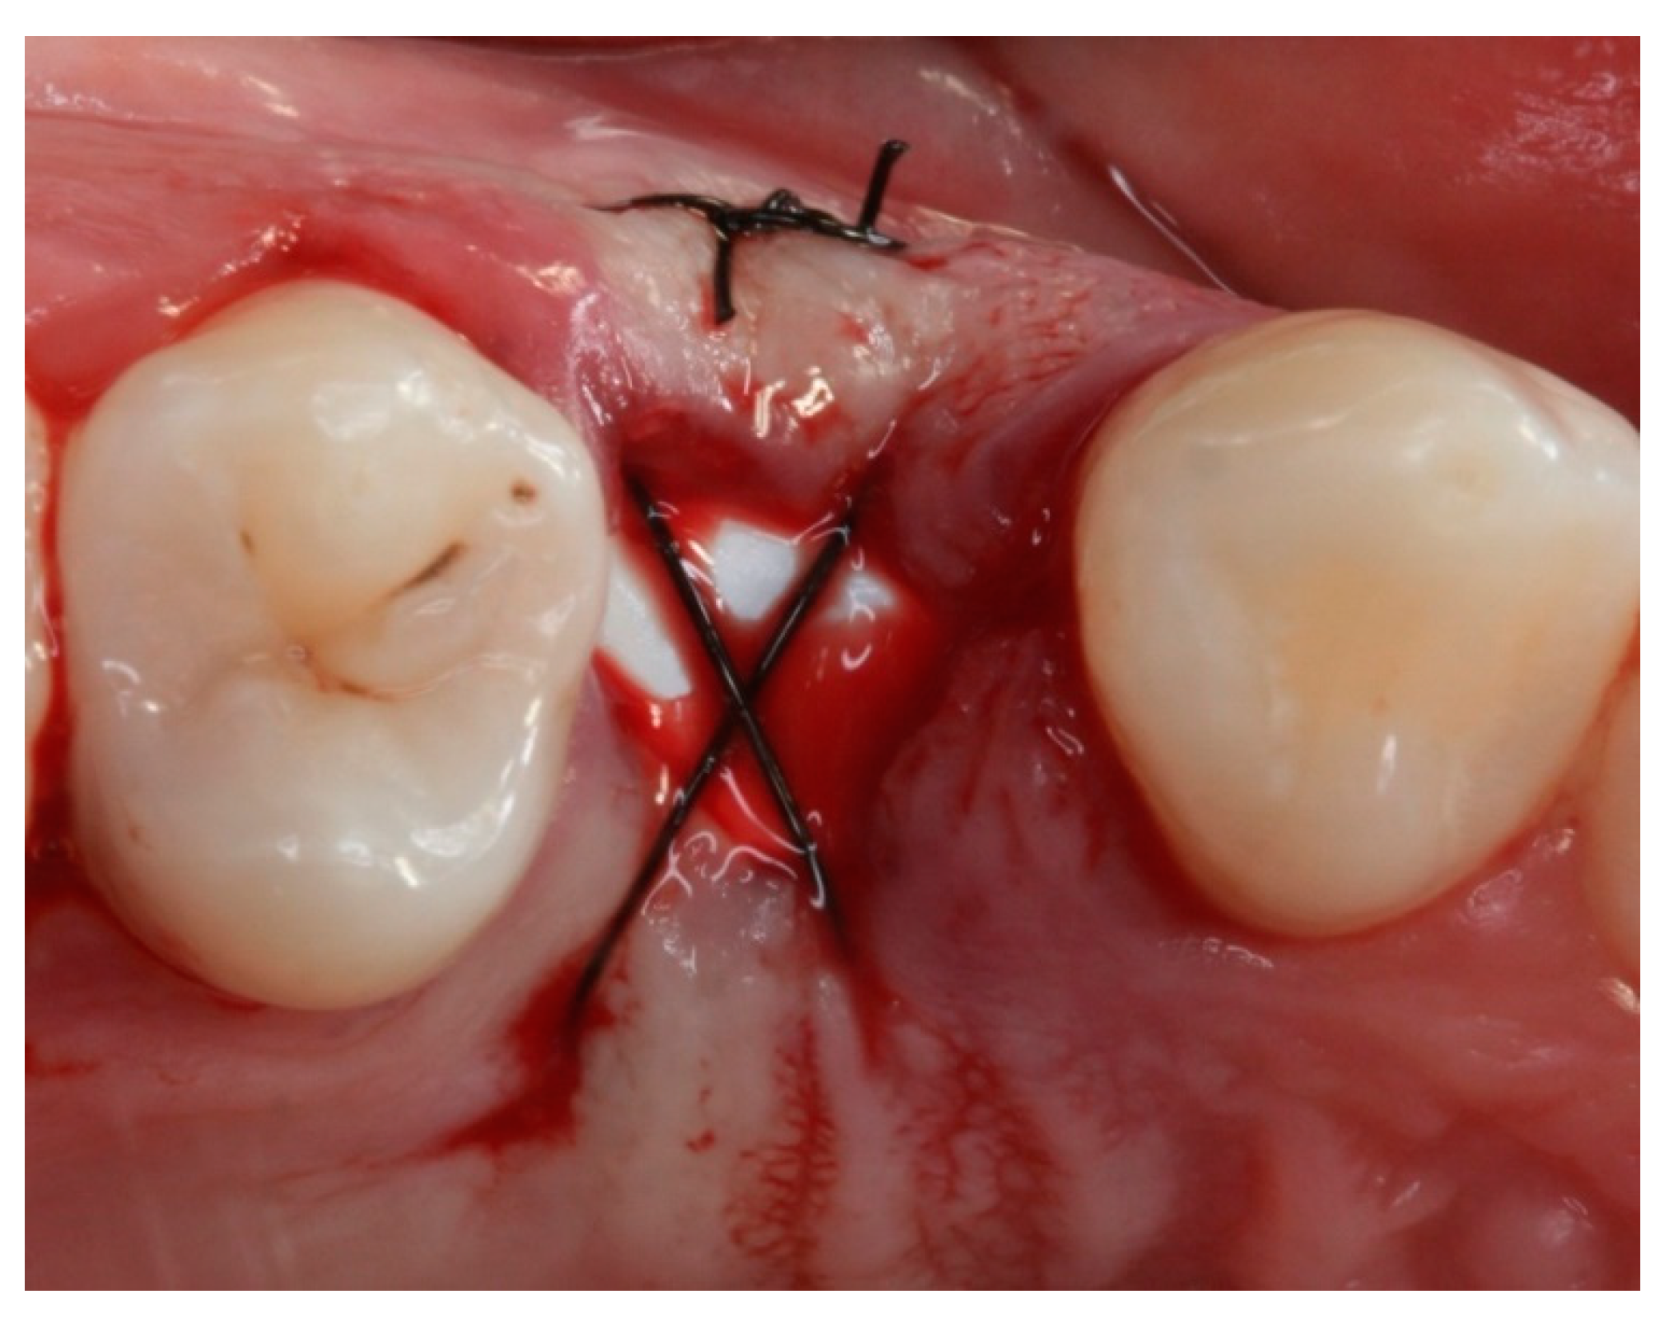

2. Materials and Methods

2.4. Groups

2.5. Post-Surgical Procedures